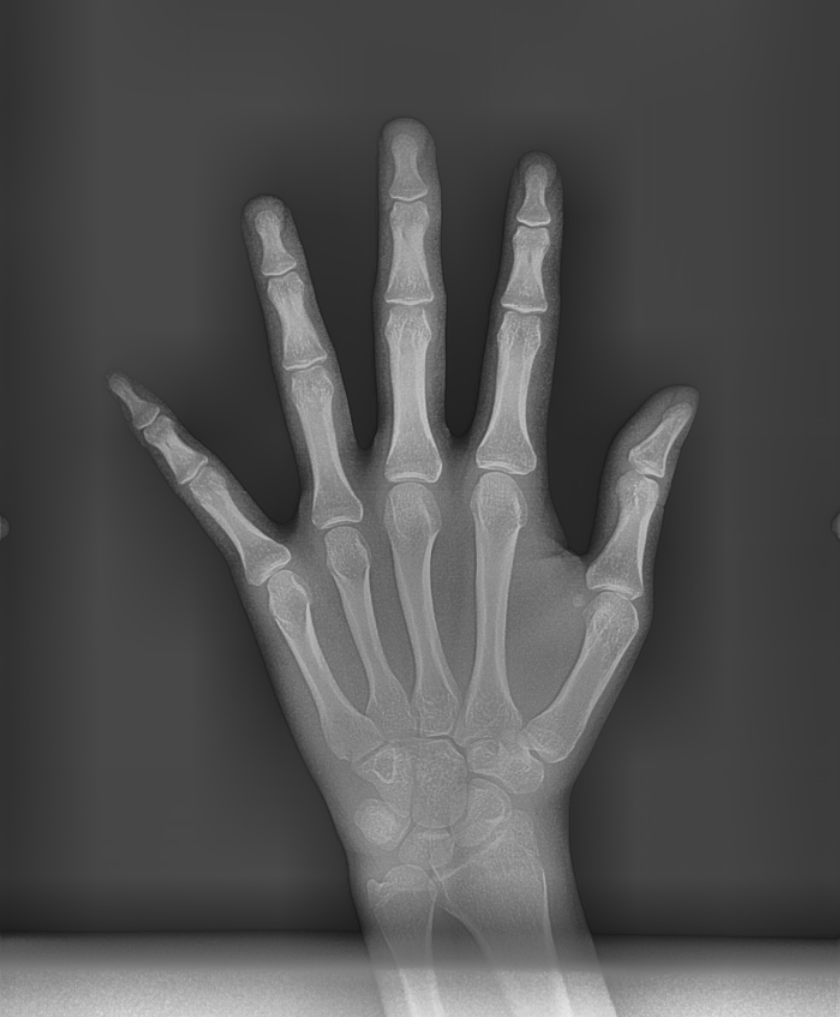

250120 성장 완료 여부를 손 사진을 통해 확인하죠